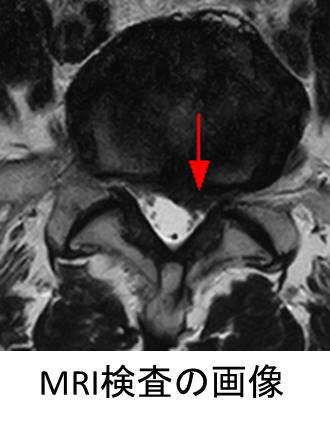

脊柱管狭窄症

腰椎椎間板ヘルニア